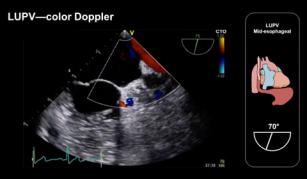

Assessing the left-sided pulmonary veins with the help of TEE 17th Oct 2017 - Andrew R. Houghton, MD [VIDEO 5:42 min] Learn how to assess the left-sided pulmonary veins using TEE. Taken from our Transesophageal ...